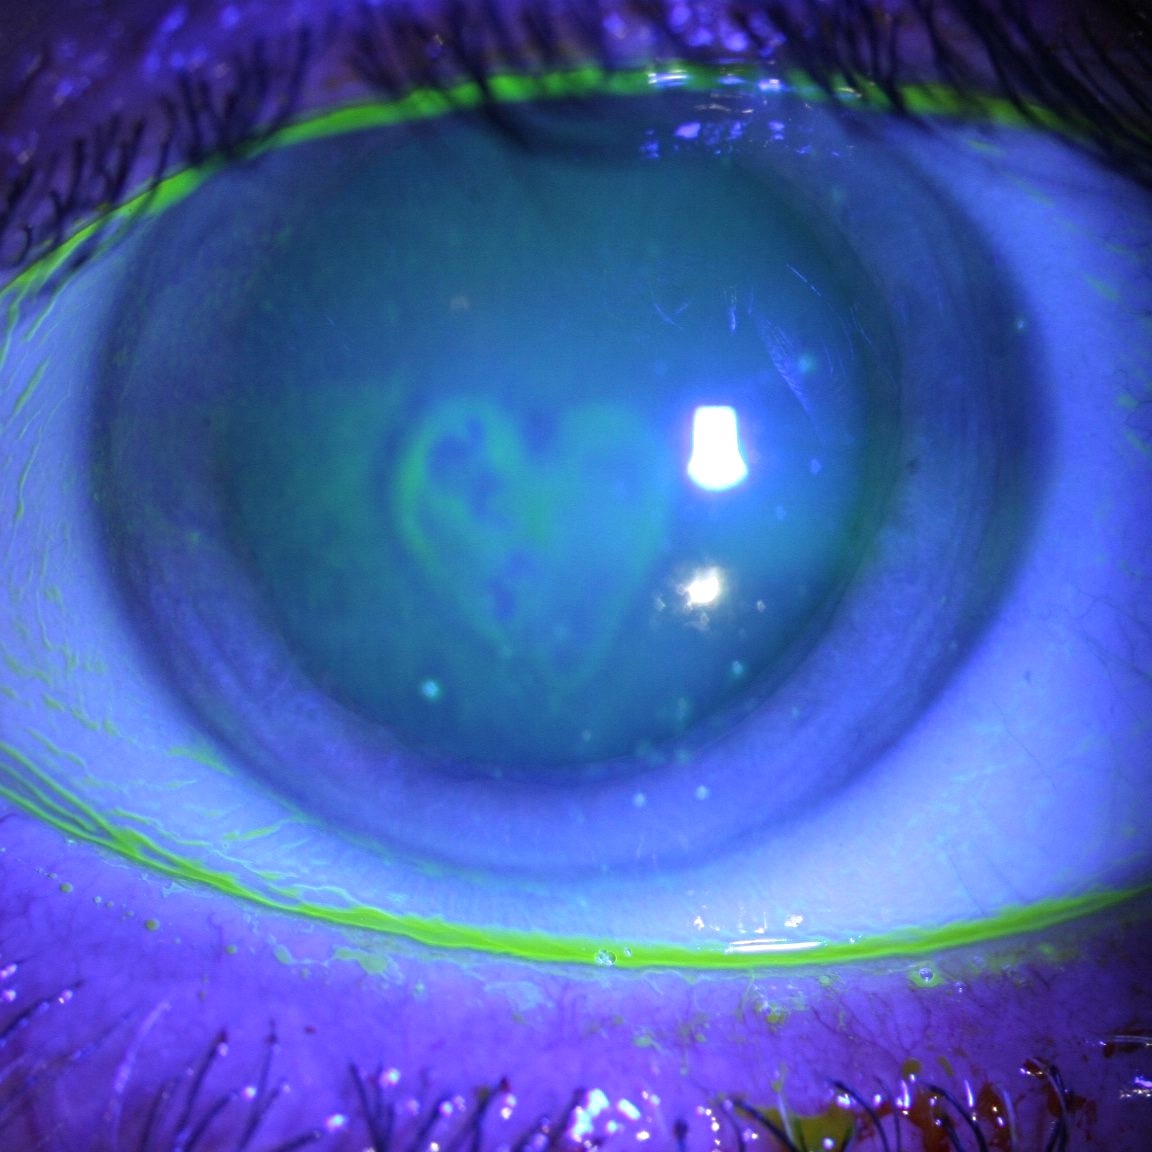

- urgences ophtalmologiques (conjonctivites, abcès de cornée, traumatismes oculaires...),

Topographie cornéenne : kératocone, astigmatisme irrégulier

Urgences ophtalmologiques : conjonctivite, abcès de cornée, traumatisme oculaire...